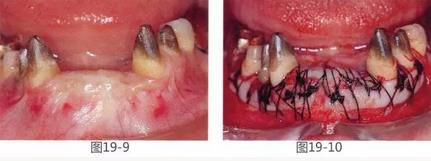

圖19-9   GBR后1年2個(gè)月的狀態(tài)。這時(shí)橋冠基牙周圍幾乎沒有附著齦,齦緣呈現(xiàn)出炎癥。

圖19-10  為了獲得基牙周圍的附著齦,在頰側(cè)以及舌側(cè)進(jìn)行FGG(游離齦移植)。